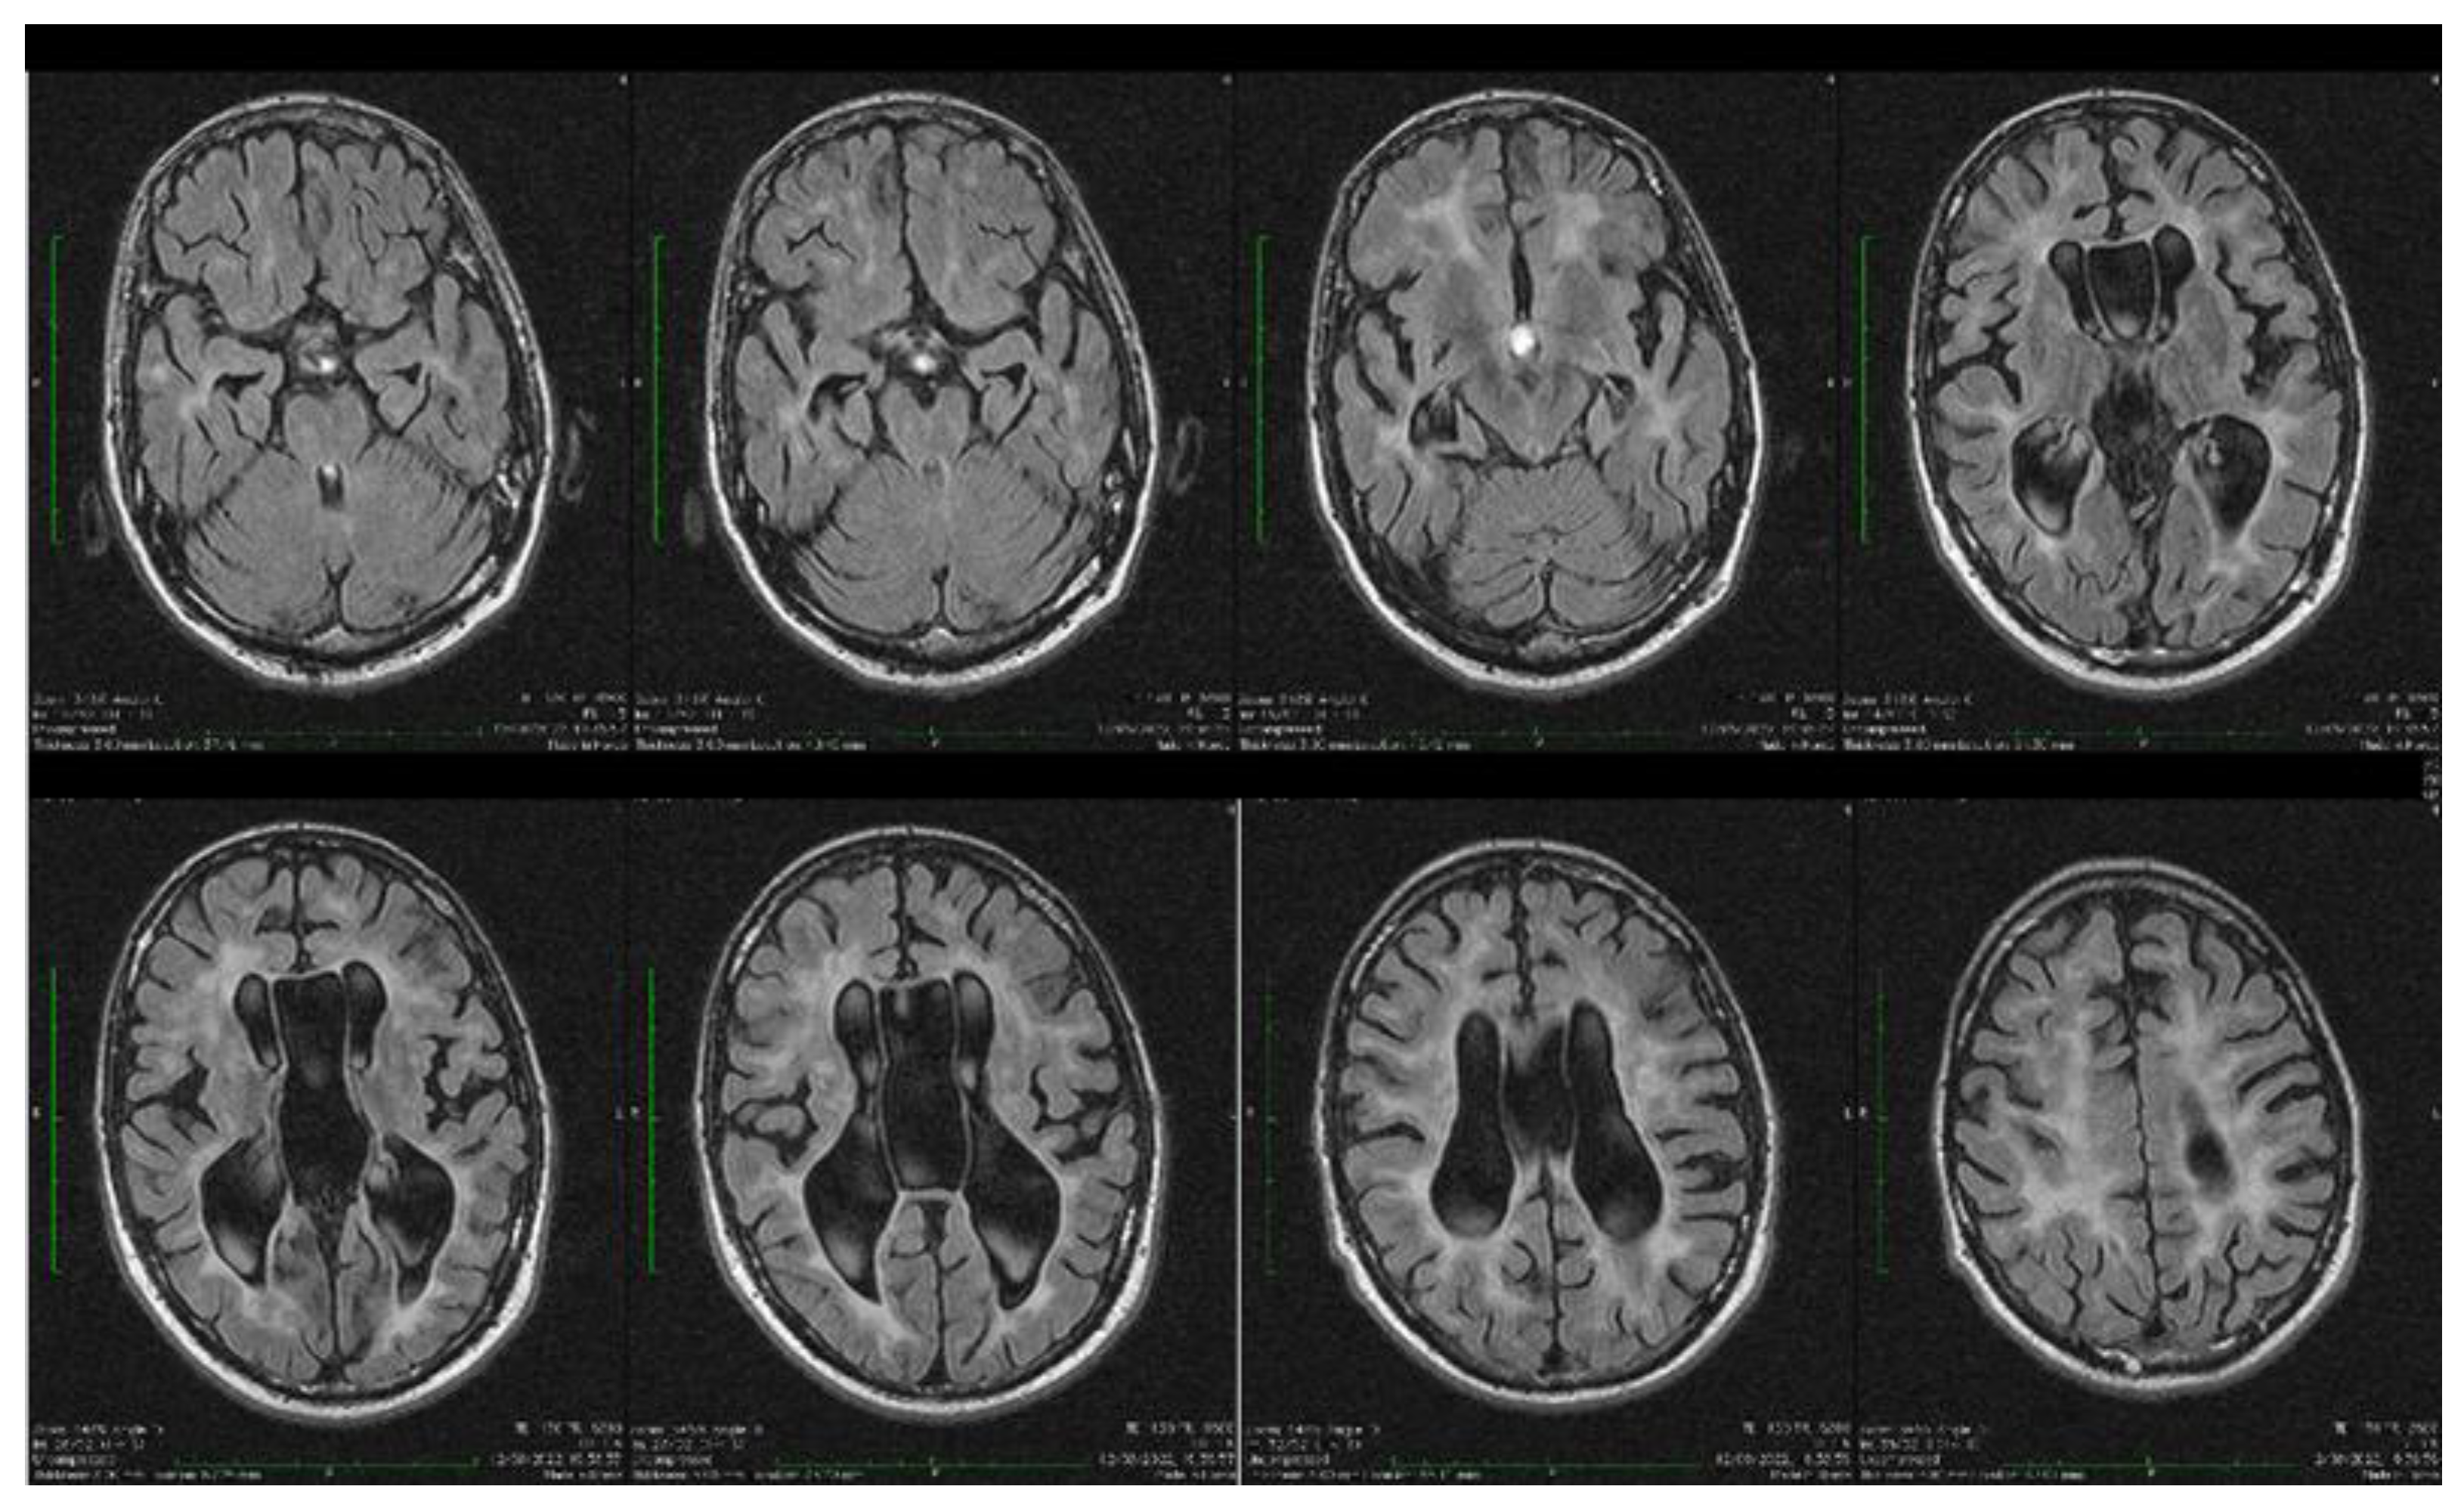

Dynamic evaluations using radiological examination were requested by various neurologists when the patient was 18 and 28 years old. The findings revealed a progressive white matter disorder with cerebral atrophy and progressive enlargement of the CSF spaces. The CT scan performed 13 years and 3 years prior to his admission to our clinic revealed generalized progressive sufferance of white matter with diffuse chronic hypodensities up to 1 cm in diameter (that were more evident at the last brain CT scan examination) at the level of the right internal capsule and lenticular nucleus, cavum septum pellucidi, an enlarged ventricular system, and progressive cerebral atrophy (Figure 2 and Figure 3). The MRI scan performed just before admission revealed severe cerebral atrophy, demyelinating lesions in the pons, middle cerebellar peduncles, supratentorial white matter with chronic lesions in the right and left temporal lobes and the right frontal and parietal lobes, marked atrophy of the right hippocampus in the context of general cerebral atrophy, cavum septum pellucidi, and severe enlargement of the CSF spaces. However, no radiological signs of active hydrocephalus were noted (Figure 4 and Figure 5).

Figure 4. Axial fluid attenuated inversion recovery (FLAIR) MRI sequences showing wide cavum septum pellucidum, enlargement of the lateral ventricles, diffuse cerebral and cerebellar atrophy, and periventricular white matter hyperintensities. The brain atrophy is even more evident compared with the previous brain imagistic investigations.